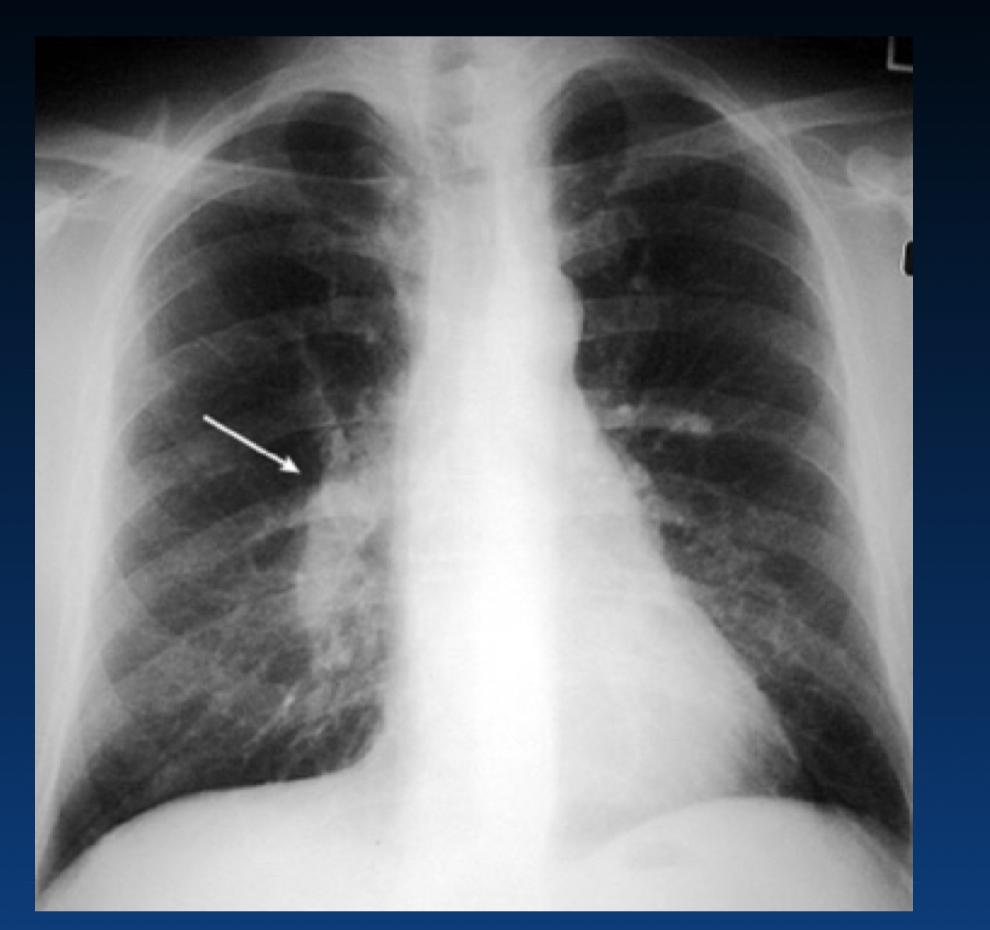

What is the Hampton hump?

How is chest x-ray used in acute pulmonary embolism?

What condition caused this? (the white arrow?)

What is the Palla sign?

What are the features of right heart strain from pulmonary embolism?